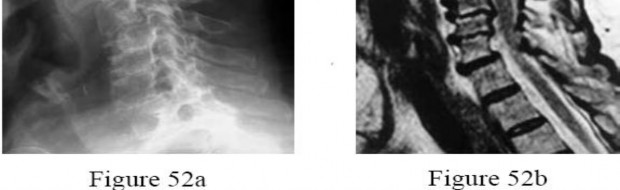

A 60-year-old male of East Asian descent presents with progressive clumsiness in his hands and an unsteady gait.

Lateral cervical radiographs reveal a continuous, dense radiopaque stripe immediately posterior to the vertebral bodies from C3 to C6. What is the most likely diagnosis?

Explanation